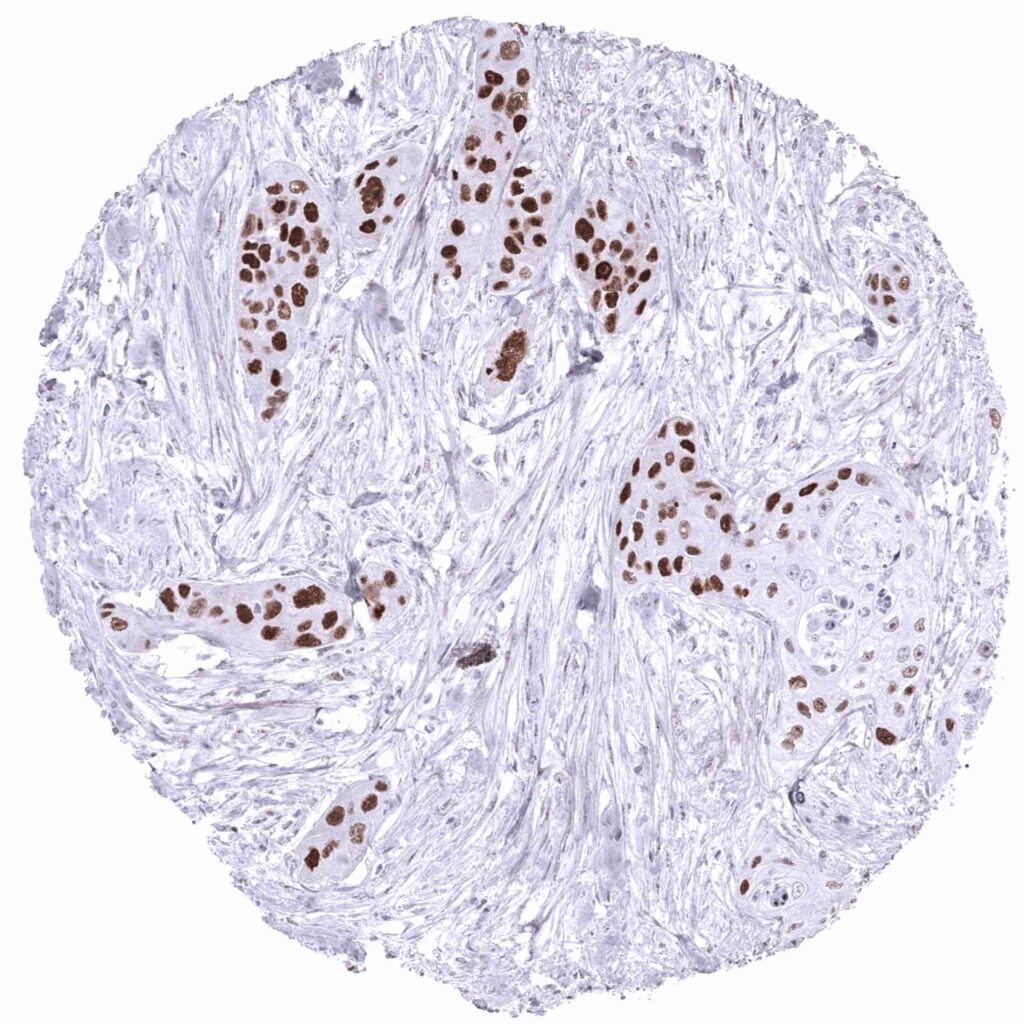

p53 antibody [MSVA-053R] HistoMAXTM

Urinary bladder- Strong nuclear p53 immunostaining of all tumor cells of a muscle-invasive urothelial carcinoma (p53 immunohistochemistry).